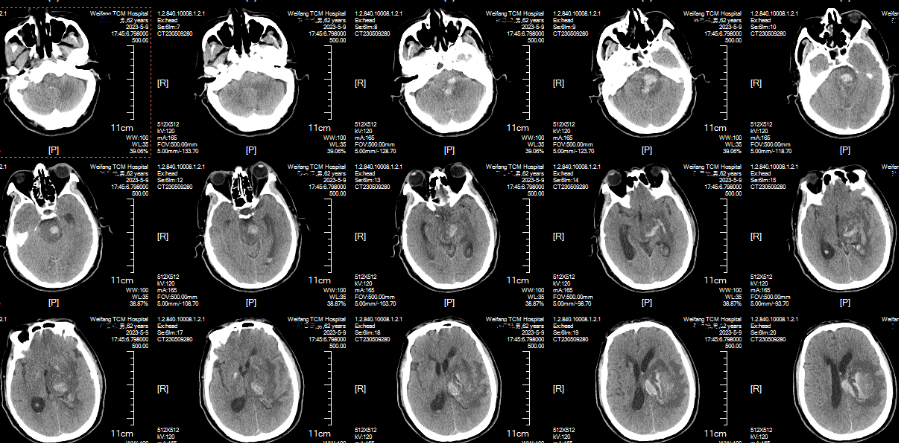

??机器人引导下脑立体定向血肿碎吸术

??在多科室的密切合作下,周垂贤主任凭借精湛的手术技能,成功实施颅内动脉瘤介入栓塞手术,将动脉瘤完全栓塞,手术第一阶段顺利完成。手术第二阶段,经过术前严密规划,神经外科团队在机器人引导下实施脑立体定向血肿碎吸手术,机器人协助让手术效率大大提升,术中抽出血肿29毫升。整个手术在2小时内顺利完成。